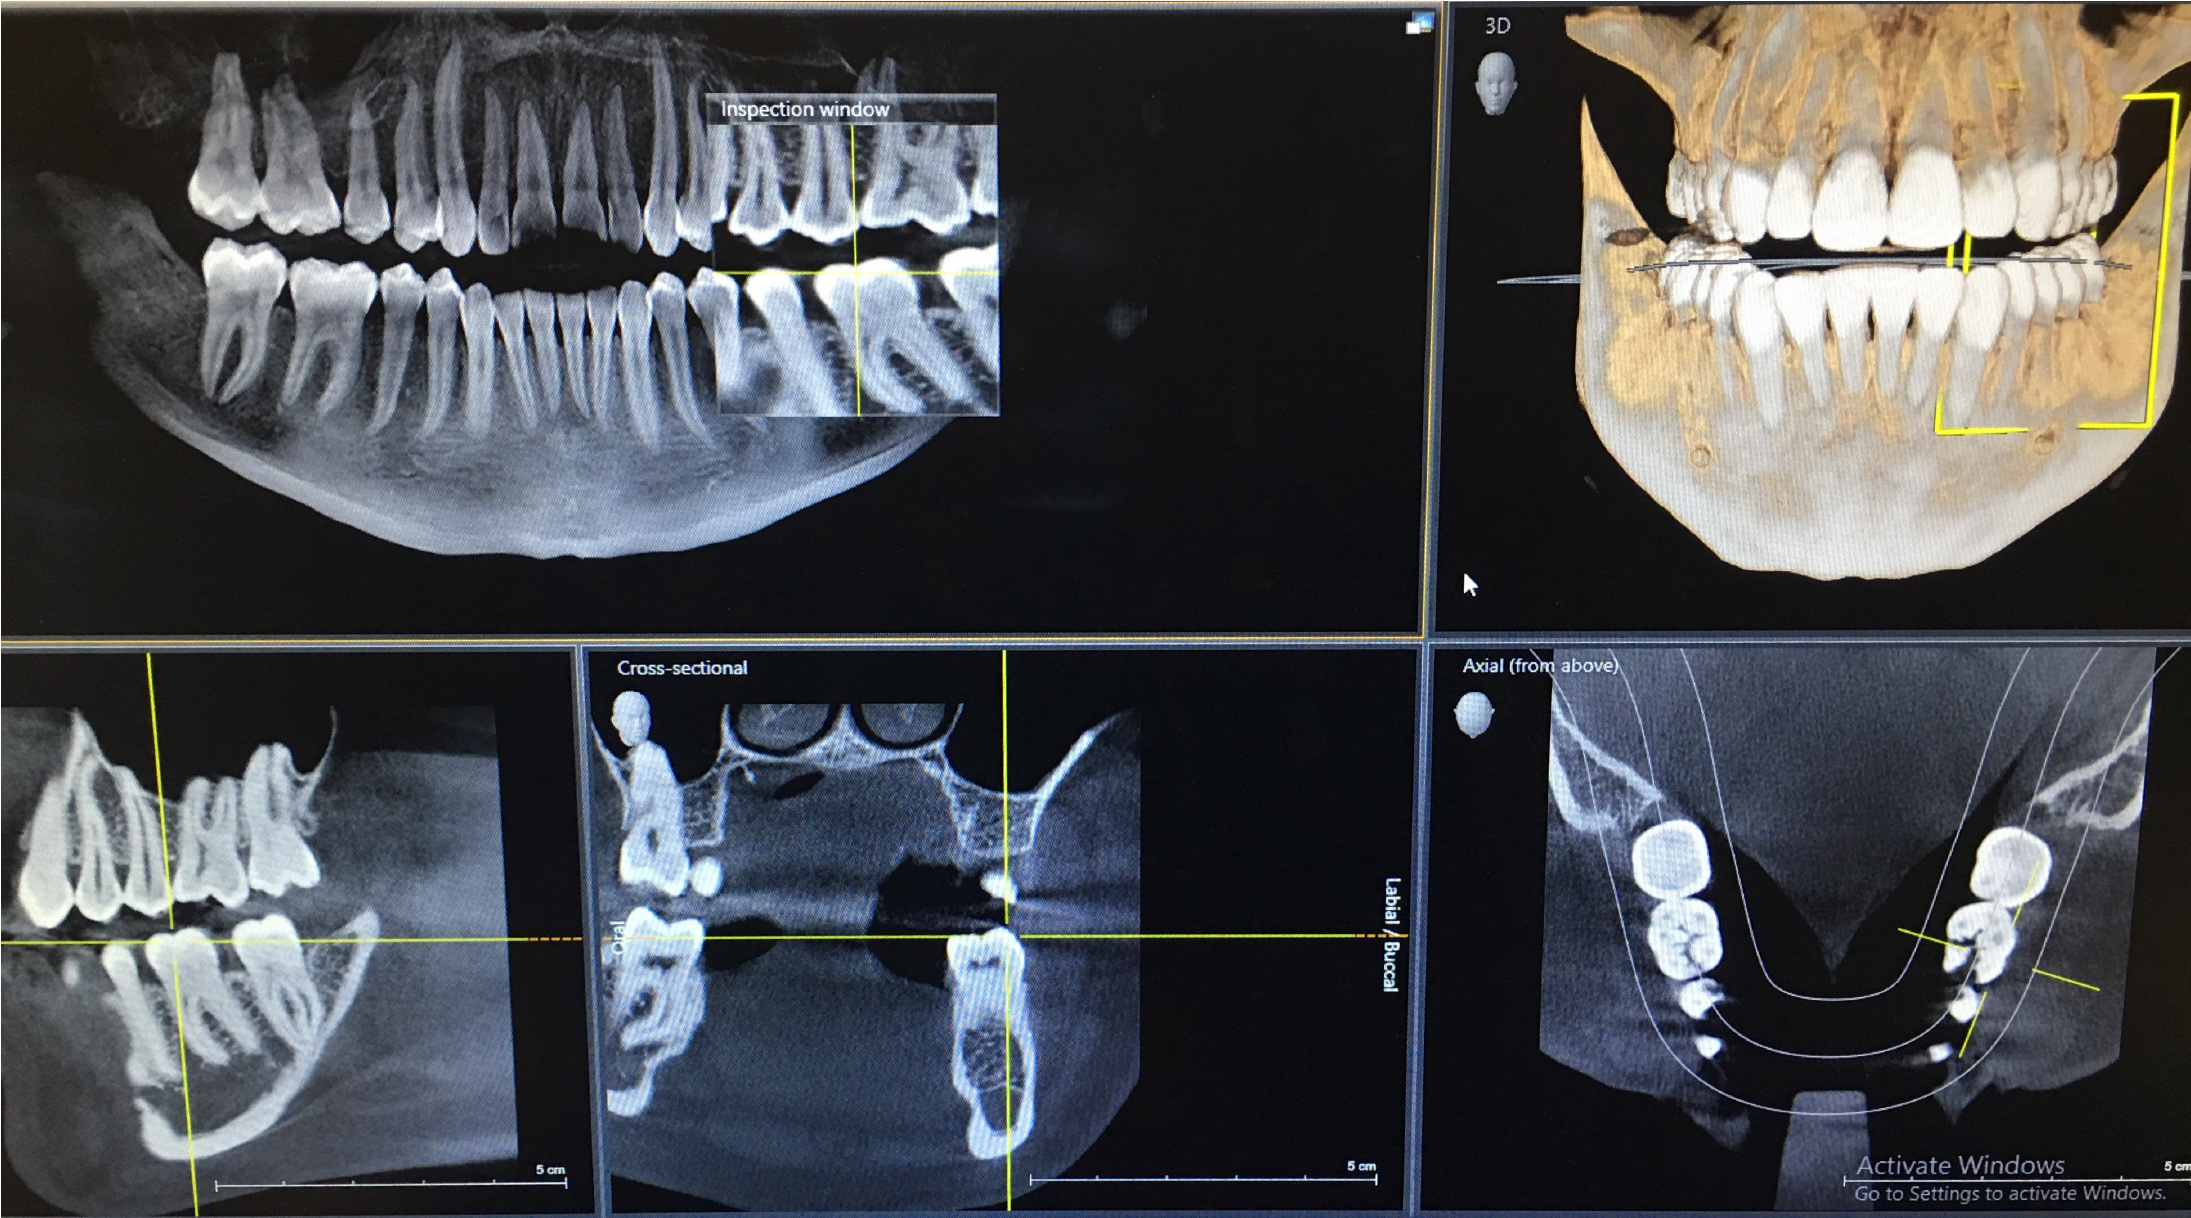

blog.digitalvolp.com.brTOMOGRAFIA COMPUTADORIZADA DE ALTA RESOLUÇÃO – CDO Radiografias

blog.digitalvolp.com.brTOMOGRAFIA COMPUTADORIZADA DE ALTA RESOLUÇÃO – CDO Radiografias